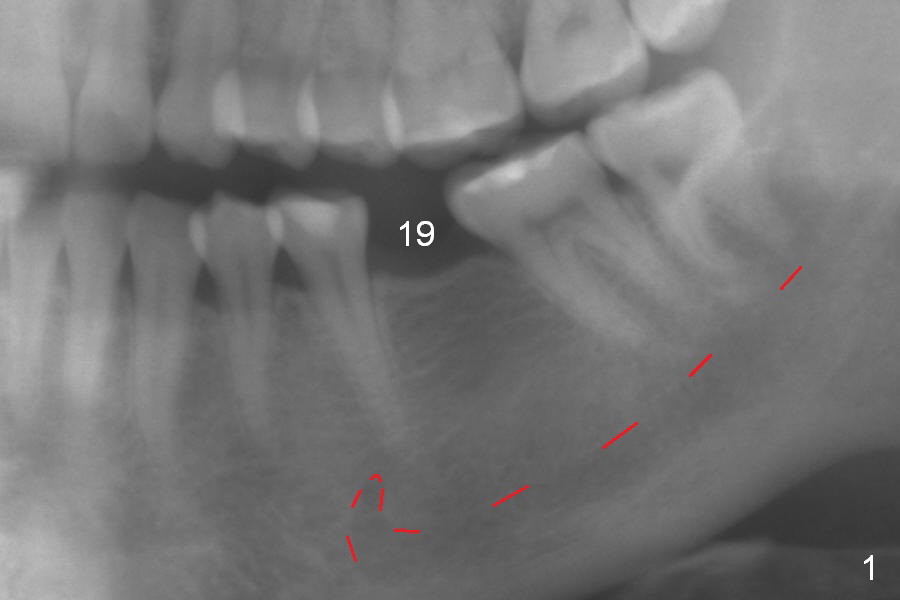

A 31-year-old woman agrees to have implant at #19 (Fig.1) after redoing MOL composite at #20 (Fig.2 *). The edentulous mesiodistal space is narrow (~ 6 mm in Fig.3). If the buccolingual bone width is found to be good after incision, a large implant is preferred. To gain space mesiodistally, the proximal surfaces of the neighboring teeth will be reduced (Fig.2 blue curved lines).

In fact, the buccolingual width of the ridge is sufficient to have a 4.5x11.5 mm implant placed (Fig.4,5, D3 bone, <35 Ncm). Proximal reduction is done before and after placement of a 5.5x4(3) mm abutment. Heavy abutment height adjustment is provided as well as the opposing prior to immediate provisional.